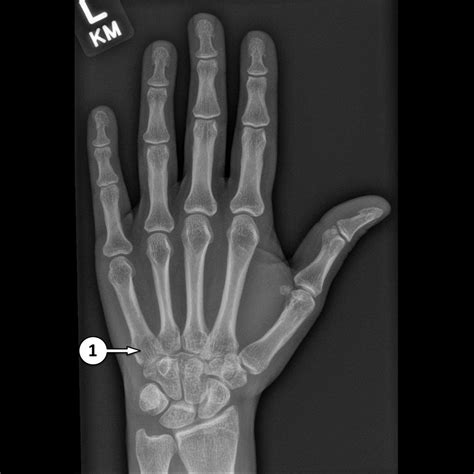

Common Indicators of an Abnormal Hand X-Ray

While you may be hoping for an X Ray Normal Hand, it is helpful to know what doctors look for when they suspect pathology. Identifying these issues early is vital for preventing long-term damage to the hand's complex mechanical system. Deviations from the norm might include:

• Fractures: A break in the continuity of the bone, ranging from subtle stress fractures to comminuted breaks.

• Dislocations: Occurring when the bones of a joint are pushed out of their normal position, often requiring immediate reduction.

• Osteoarthritis: Characterized by the loss of joint space and the presence of osteophytes, or bone spurs.

• Bone Cysts or Tumors: Rare findings that appear as lucencies or dark, irregularly shaped areas within the bone structure.

💡 Note: If you experience persistent pain or swelling despite a normal radiographic report, consult with your healthcare provider about secondary imaging, such as an MRI or ultrasound, which are better suited for evaluating tendons and ligaments.

Importance of Professional Interpretation

The interpretation of medical imaging is a highly specialized skill. Even if you look at your own X Ray Normal Hand and see what appears to be a clear image, small nuances—such as a sesamoid bone variation or an accessory ossicle—can easily be misidentified by an untrained eye. Radiologists and orthopedic specialists have years of training to distinguish between anatomical variants, which are normal differences in bone shape, and actual pathological conditions.